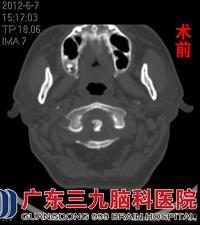

刘先生初次来院时入住医院神经康复科,见治疗效果不佳,康复科邀请脊髓神经外科专家会诊。经专家详细询问病史了解到,刘先生5年前曾患有结核性胸膜炎,根据其入院后的颈椎CT、MRI检查提示环椎周围、齿状突后方硬膜外软组织增厚,拟炎症性病变,齿状突骨质受累破坏;环枢关节半脱位;环枢关节前间隙少许积液;C1平面椎管狭窄,脊髓受压,未见变性。化验单示5月20日血沉50mm/h、C-反应蛋白4.97mg/dl,遂进一步诊断为:1、枢椎齿状突结核并环枢关节半脱位2、颈椎病。www.999brain.com

CT是早期诊断极有效的方法,CT能清晰地显示骨的破坏和软组织肿胀影,尤其是在早期,能显现较局限的病变,结合病史,考虑为枢椎齿状突结核,行抗结核治疗,颅骨牵引10天后改头颈胸支具固定,加强营养支持治疗,主诉颈痛症状缓解。于2012年6月14日在全麻下行颈椎后路减压复位枕颈融合椎根弓钉棒系统内固定手术治疗,术后复位固定良好,出院后继续行抗结核治疗。10个月后复查CT示颈椎内固定术后改变,环枢关节间隙正常,齿状突低密度影消失,骨质破坏已修复。患者已无头颈部胀痛、饮水呛咳等症状,四肢感觉肌力正常,活动正常。www.999brain.com